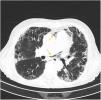

Más datosMujer de 72 años con tos crónica por enfermedad pulmonar intersticial severa y fibrosis. Fue encontrada al despertar en coma, escala de coma de Glasgow 3, desviación de la mirada a la izquierda, hipotonía generalizada, pupilas anisocóricas con midriasis derecha, TC de tórax: pequeño neumotórax apical izquierdo y presencia de aire ectópico en mediastino superior (flechas) (fig. 1), TC cerebral: numerosas burbujas aéreas que se disponen en los surcos cerebrales (flechas), así como áreas hipodensas córtico-subcorticales de distribución parcheadas en áreas parietooccipitales bilaterales (fig. 2). El mecanismo implicado que podría explicar nuestro caso (en ausencia de foramen oval permeable) sería el shunt intrapulmonar. Un aumento brusco de la presión intratorácica por maniobras de Valsalva junto con la producción del neumotórax y el neumomediastino sobre un pulmón patológico podría facilitar el paso de aire a las venas pulmonares y de ahí al sistema circulatorio izquierdo provocando embolismos aéreos en el cerebro.